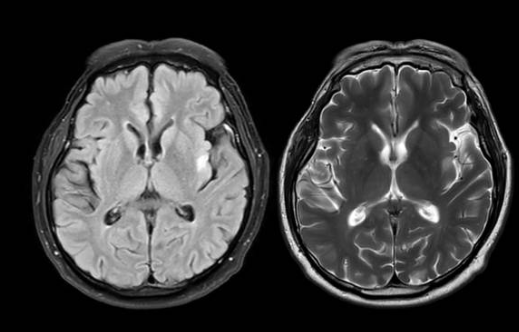

파킨슨병은 뇌의 특정 부위에서 도파민이라는 신경전달물질이 부족해지면서 생기는 만성 신경계 질환입니다.

도파민은 우리 몸의 움직임을 부드럽고 자연스럽게 조절하는 역할을 합니다. 그런데 이 도파민을 만들어내는 신경세포가 점점 줄어들면 몸의 움직임이 느려지고, 떨림이나 근육의 뻣뻣함 같은 증상이 나타나게 됩니다.

가장 핵심적인 원인은 도파민을 만드는 뇌신경세포가 점점 사라지는 것입니다. 이 세포가 줄어들수록 몸의 움직임을 조절하는 기능이 약해집니다.